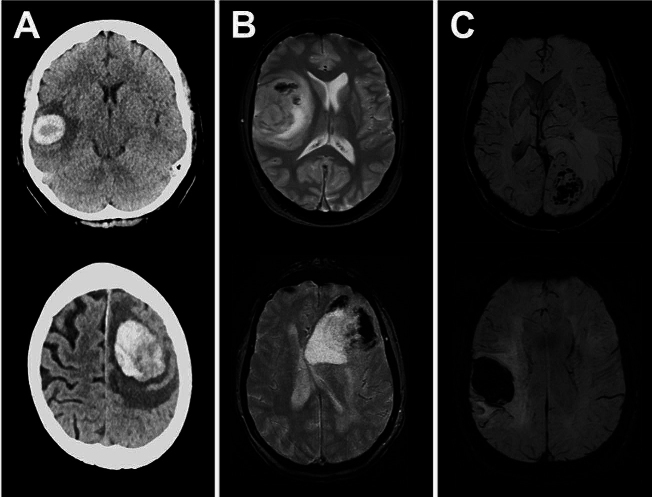

In a large subgroup of patients (N = 54, 23.6%), metastasis-associated hemorrhage was evident on preoperative imaging. Exemplary cases are illustrated in Fig. 1. In these 54 cases, most patients suffered from metastases of lung carcinoma (N = 23, 42.6%) or melanoma (N = 14, 25.9%), while the incidence of breast cancer metastasis (N = 1, 1.9%) was very low. For all entities, melanoma (N = 14, 58.3%) showed the highest incidence of BM-associated hemorrhage, and diagnosis of melanoma metastasis was associated with tumor-related bleeding in univariate analysis (OR = 5.78, 95%CI = 2.39–13.95, p = 0.001). On the other hand, the overall incidence of hemorrhage for breast cancer patients was low (N = 1, 4.35%) and diagnosis of breast cancer was associated with the lack of bleeding in univariate analysis (OR = 0.13, 95%CI = 0.02–1.00, p = 0.034). Moreover, poor clinical status, as measured by a KPS score of < 70 (OR = 30.26, 95%CI = 3.69–248.13, p = 0.001), and impaired prognosis, as measured by an RPA score of > 2 (OR = 30.26, 95%CI = 3.69–248.13, p = 0.001), were associated with a higher risk of bleeding events in the univariate analysis. Furthermore, larger metastases revealed a higher risk for tumor-associated hemorrhage (p = 0.044). One-fourth of all patients (N = 57, 24.9%) were treated preoperatively with blood-thinning medications, but there was no association between preoperative use of these drugs and the occurrence of tumor-associated bleeding (OR = 0.90; 95%CI = 0.518–1.563; p = 0.426). Table 2 illustrates the results of univariate analyses and highlights the predictors for BM-related hemorrhage.

Fig. 1.

Exemplary cases of patients with hemorrhagic BM. Shown are 6 different patients with hemorrhagic brain metastases, using (A) CT imaging, (B) MRI / GRE-T2* imaging, and (C) MRI / SWI imaging. The axial slices are shown